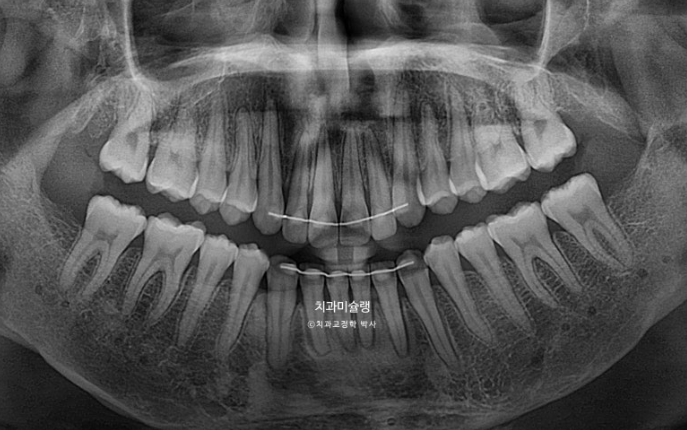

치근흡수는 없으며 치근평행도는 양호합니다.